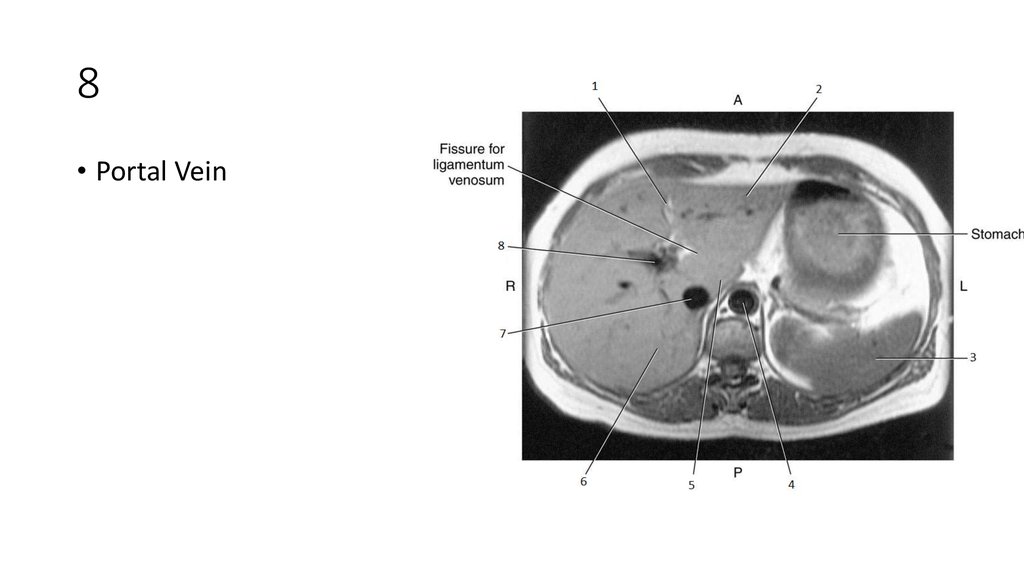

30. 8

31. 8

• Portal Vein